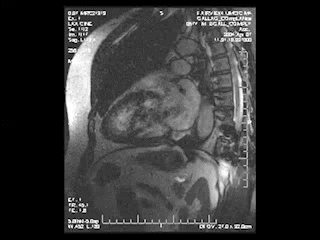

心臓MRI検査

MRIにより心臓の筋肉の状態や動きを見る検査。シネMRI撮影では心臓の動きを動画で確認ができます。

出典: the University of Minnesota | Atlas of Human CARDIAC Anatomy

http://www.vhlab.umn.edu/atlas/index.shtml